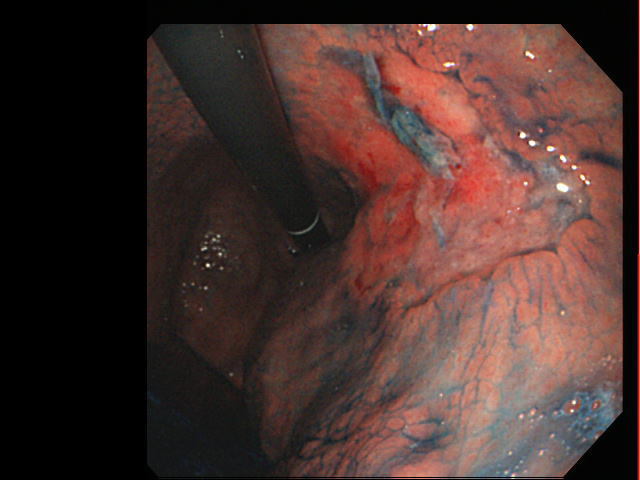

胃カメラ

胃がんの診断は、胃X線検査や胃カメラで行います。胃がん検診や胃痛などのおなかの症状がある方が、検査を受けます。胃X線検査で異常が見つかった場合、やはり胃カメラにて精密検査を行います。検査にて、胃に何らかの病変が見つかった時、生検(病変の一部の組織を採取すること)を行い、組織検査をして、がんがどうか確定します。